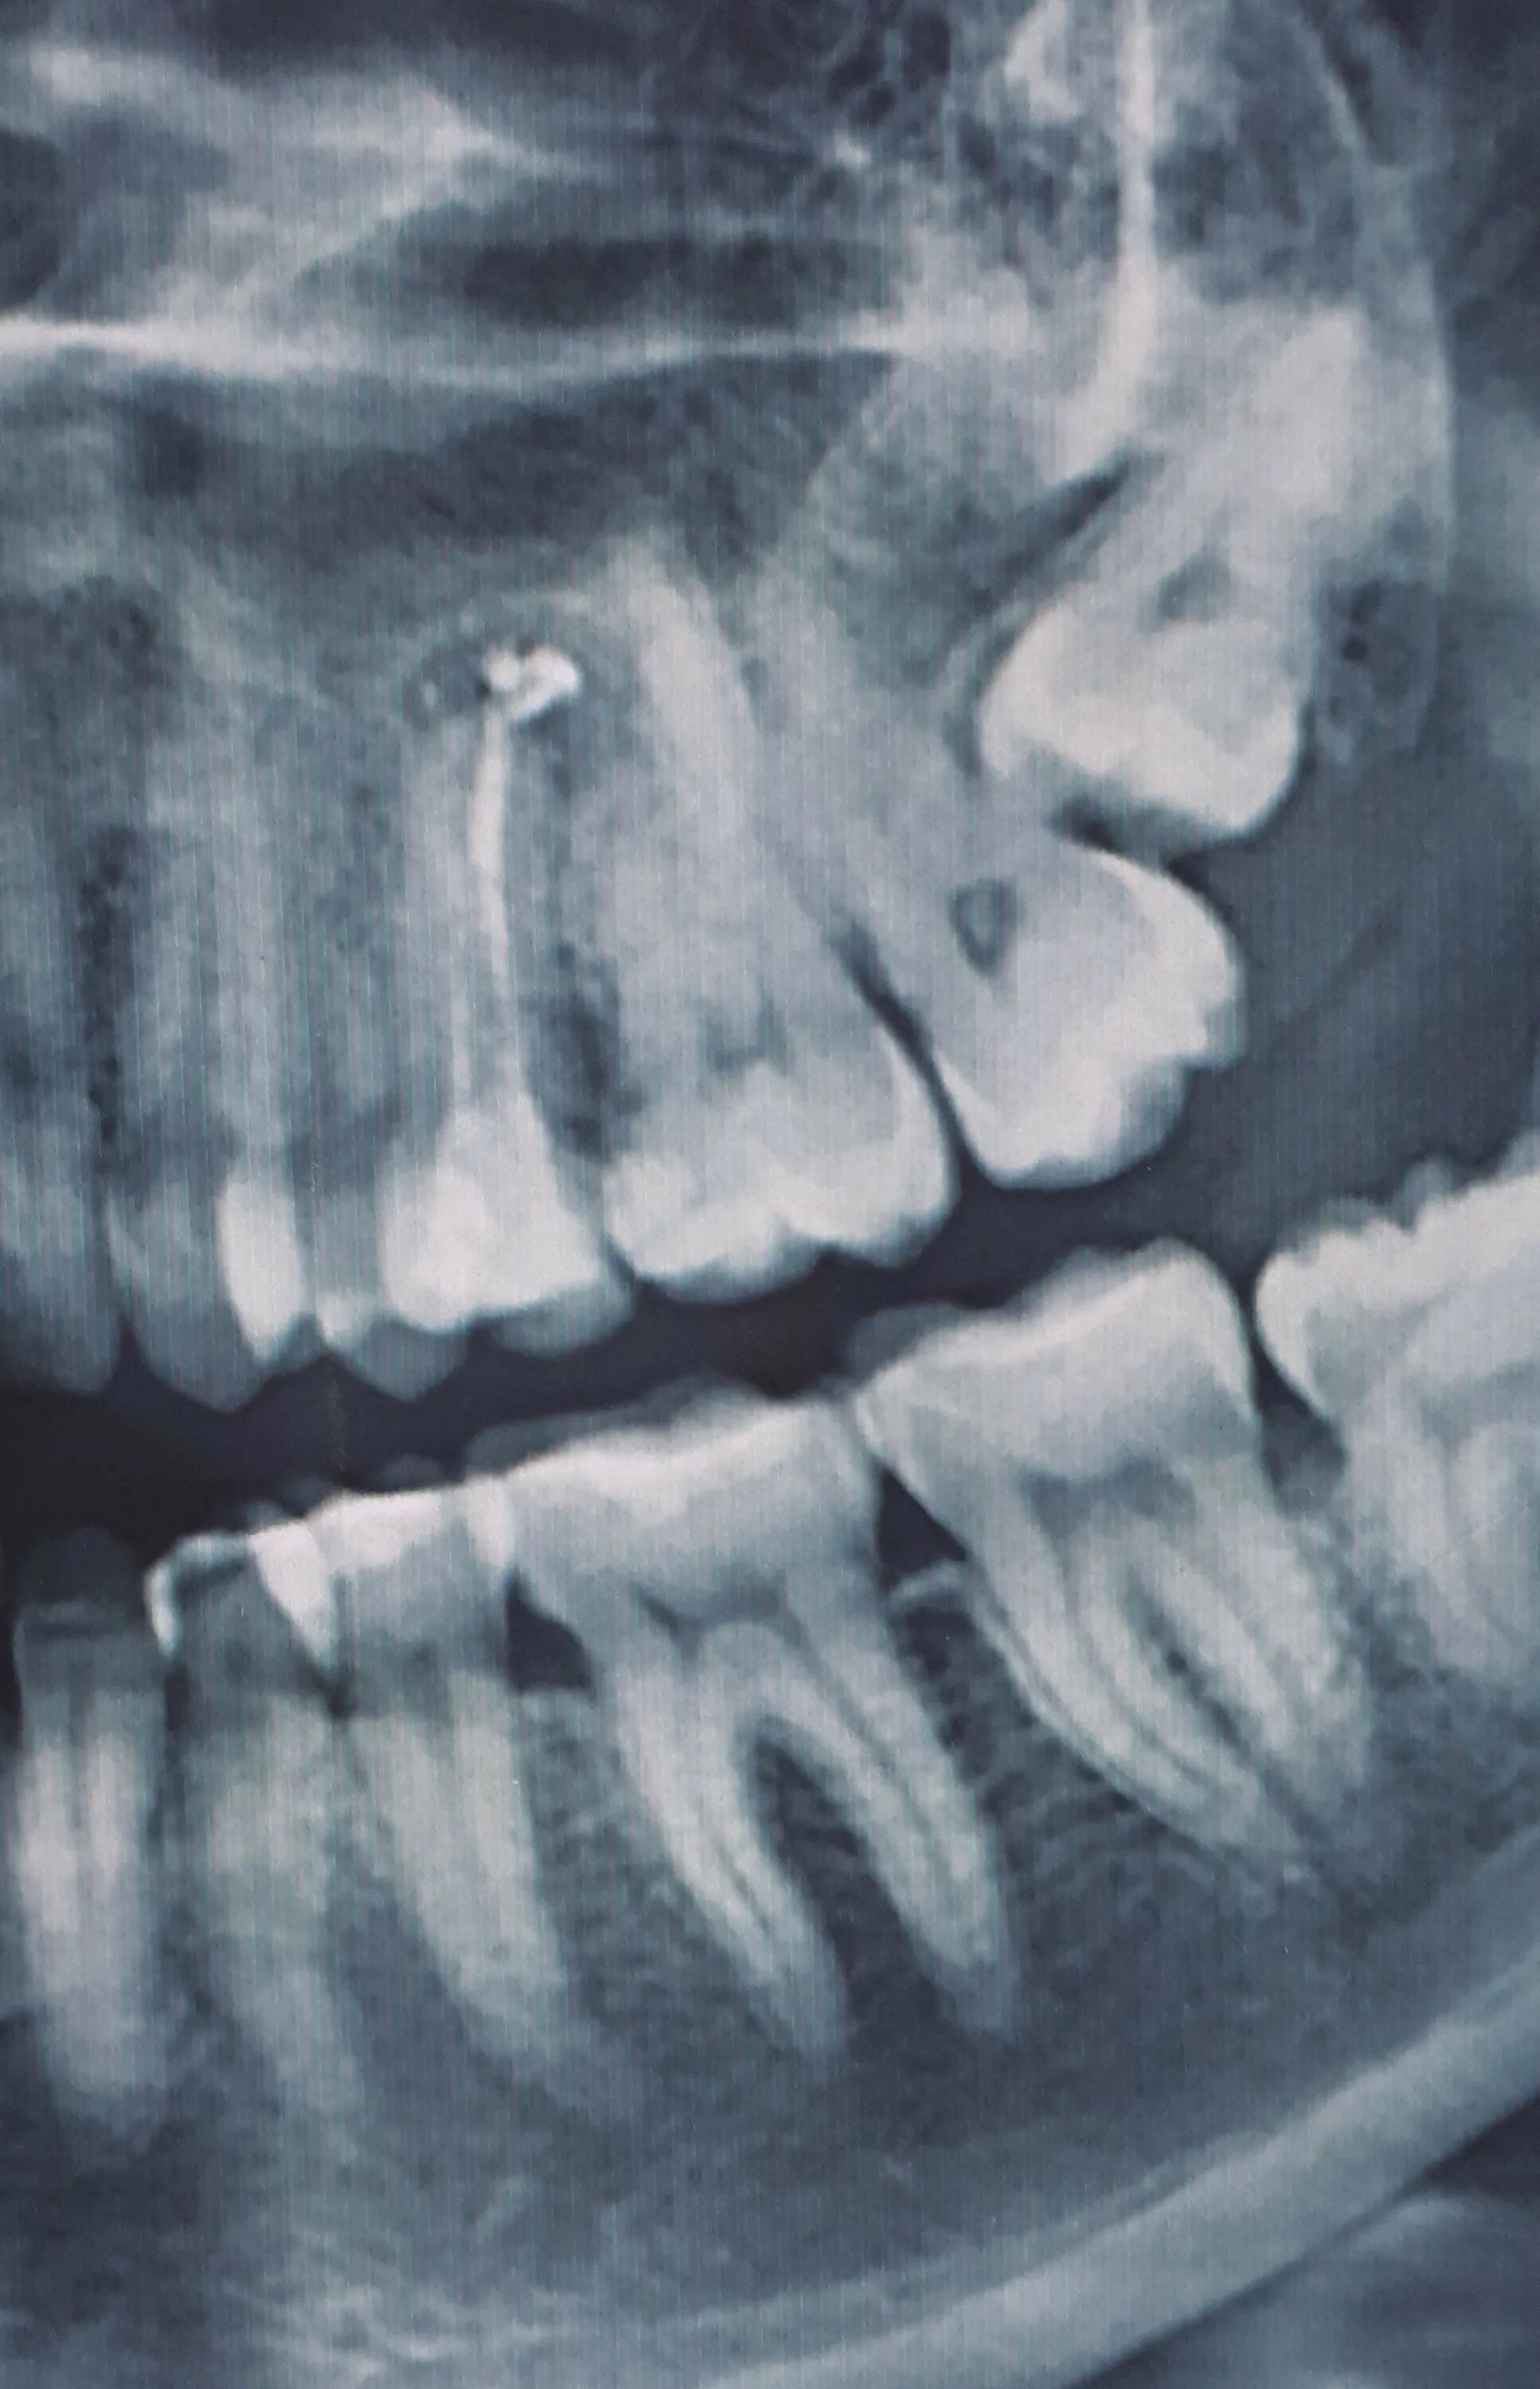

Киста зуба что это